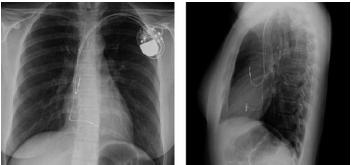

Uma paciente com história de síncope e períodos de bloqueio atrioventricular total foi submetida a implante de marcapasso definitivo.

De acordo com sua radiografia de tórax, o tipo de dispositivo mais provável é o